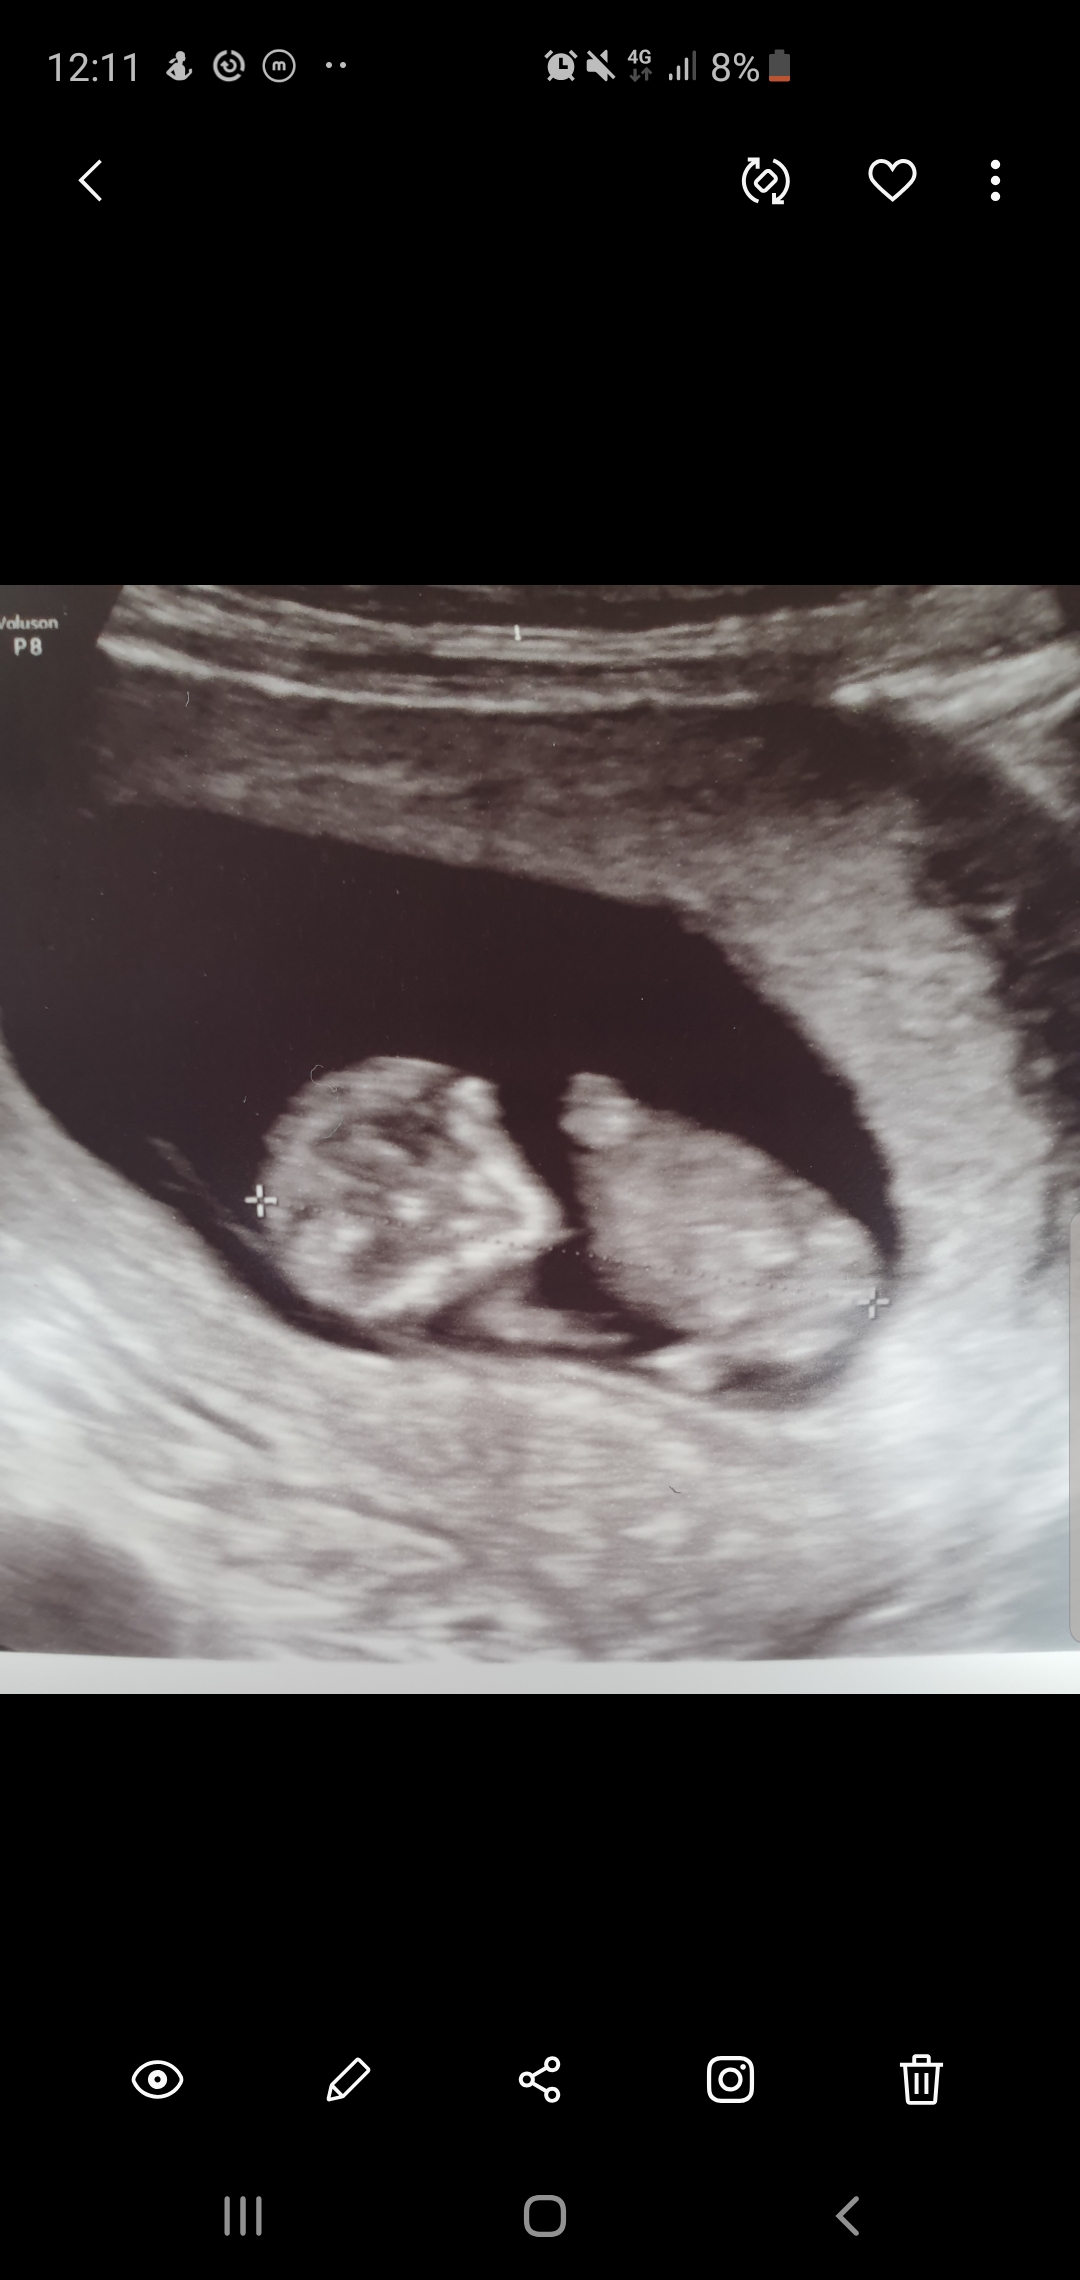

For the nub, you need a profile picture from the baby and 11+4 is too early for accuracy. Sweet baby though

I was thinking ramzi theory.. is that the umbilical cord to the left ? Would that mean boy?

Too late for Ramzi...

Ramzi is meant for around 6-7 weeks so this is too late. It's an inaccurate method anyway.

The reason you can't do Ramzi so late is because the placenta grows and the direction it grows may not be at all indicative of where it started out at. So you can't tell where the implantation really occurred later on.